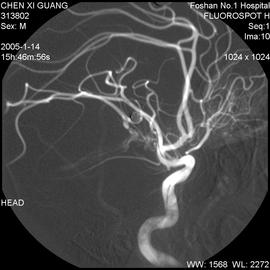

•血管造影:1至3小时

图片来源于网络

血管造影:注入造影剂有时会有温暖或灼热的感觉。造影剂可能引起恶心,呕吐,潮红,瘙痒或口苦等症状。在极少数情况下,人们会对造影剂产生严重的过敏反应,影响患者的呼吸和血压。造影剂也会引起肾脏问题,这种情况很少见,但在肾功能不全的患者中较常见。

该检查存在一种小风险的可能,就是在导管末端有可能会形成血凝块的,阻塞血管。导管损伤血管的风险也很小,但这可能导致内出血。如果按压时间过短,可能会导致创口出现血肿(皮肤下聚集大量血液)。除此之外,创口部位可能存在感染的几率。